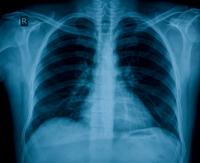

Delayed Access to Tertiary Care Associated with Higher Death Rate from Type of Pulmonary Fibrosis

Idiopathic pulmonary fibrosis (IPF) -- scarring and thickening of the lungs from unknown causes -- is the predominant condition leading to lung transplantation nationwide. Columbia University Medical Center researchers confirmed that delayed access to a tertiary care center for IPF is associated with a higher risk of death. The findings were published online in the American Journal of Respiratory and Critical Care Medicine on June 30, 2011.

A group led by Columbia researcher David J. Lederer followed 129 IPF patients at an academic medical center. They looked at the length of time from the onset of shortness of breath to the first visit to the center. A longer delay was associated with increased risk of death, independent of age, gender, socioeconomic status, lung capacity, disease severity, type of health insurance, or education. The researchers also found no association between the length of delay and the likelihood of the patient’s receiving a lung transplant. IPF leads to respiratory failure and death, usually within three years. It is a relatively rare disease, which afflicts 100,000–120,000 Americans, almost all over the age of 50. Characterized by shortness of breath upon exertion, it is often misdiagnosed, especially in people with other ailments. A delay in making a correct diagnosis can lead to ineffective, or even harmful, treatments. For example, doctors sometimes still treat IPF with steroids, because the disease was originally thought to have an inflammatory component. Now scientists know that steroids are counterproductive. A delay in diagnosis can also delay evaluation for a lung transplant. Although research is underway on potential drug therapies, currently lung transplantation is the only effective treatment. “The initial symptoms of IPF are subtle, and accurate diagnosis may not be feasible for community-based pulmonologists,” explains Lederer, Herbert Irving Assistant Professor of Clinical Medicine and co-director of the New York-Presbyterian Hospital Interstitial Lung Disease Program and Lung Transplant Program. For that reason, earlier access would be aided by improved methods of early detection. But until then, the recognition, or even suspicion, of IPF should prompt referral to a tertiary care center. The study’s authors are Daniela J Lamas (CUMC), Steven M. Kawut (University of Pennsylvania), Emilia Bagiella (CUMC), Nisha Philip (CUMC), Selim M. Arcasoy (CUMC), and David J. Lederer (CUMC). The study was supported by the NIH, the Robert Wood Johnson Foundation, and Herbert and Florence Irving. DL serves as an advisor to Gilead Sciences, Inc. The other authors declare no financial or other conflict of interest.